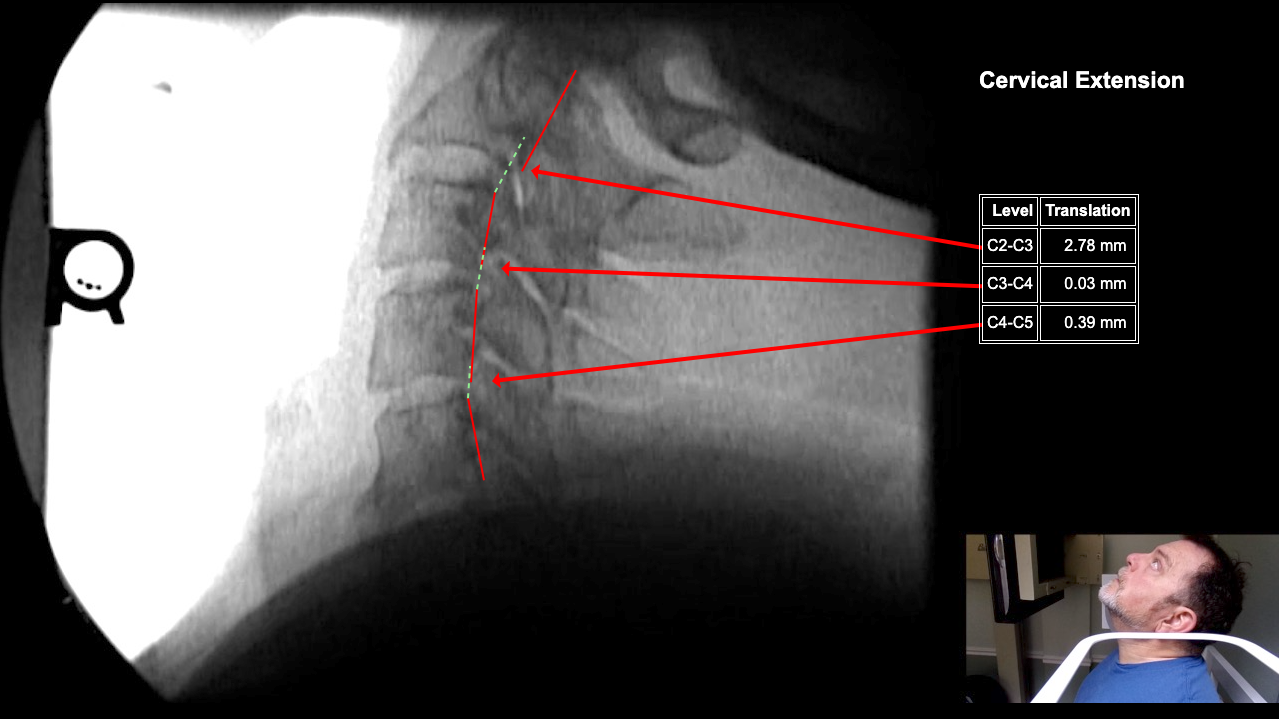

Image 2